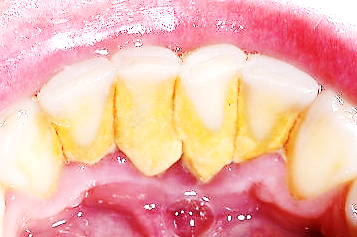

치석이 생기는 이유 원인

치석은 치아 사이에 생기는 돌조각입니다.

치석이 만들어지는 원인은 식사 후에 치아와 잇몸 경계 부위 그리고 치아 사이에 양치로 제거되지 않은 음식물 찌꺼기와 프라그가 남게 되는데요.

오랜 시간이 지나면서 침 속의 칼슘, 인과 반응해서 돌처럼 굳어 치석이 됩니다.

치석 위에 다른 음식물 찌꺼기가 계속 달라붙어 점점 커지게 됩니다.

치석은 잇몸질환의 가장 근본적인 원인이고 첫 번째 원인이 됩니다.

치석 표면은 거칠어서 프라그가 쉽게 붙을 수 있는 장소가 됩니다.

프라그는 세균덩어리입니다. 잇몸질환을 유발하는 주된 원인이기 때문에 프라그가 잘 생길 수 있는 치석을 제거하는 관리는 꼭 필요합니다.

잇몸과 치아 경계에 치석이 생기면 염증이 생기기 쉽고 이로 인해 잇몸이 민감해져 혈관이 확장되어 통증과 출혈이 생길 수 있습니다.